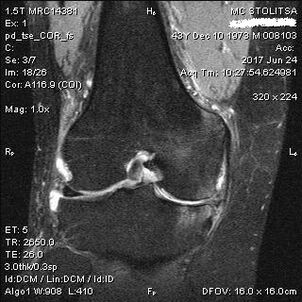

Diagnosis of knee arthritis is made in the office of a rheumatologist or orthopedic surgeon.The doctor examines and palpates the affected joints, listens to complaints, and asks other questions.Perform multiple tests - for example, asking the patient to bend their legs or take a few steps.He will then refer you for further studies if the stage of the disease or the nature of the pathological changes needs to be clarified.For example, for computed tomography or radiography.